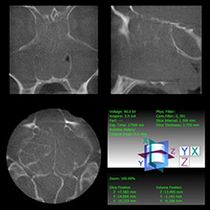

Chronisch-polypöse Sinusitis mit Verlegung sämtlicher Nasennebenhöhlen und der Nasenhaupthöhle (Digitale Volumentomographie, DVT)

Die Diagnostik dieser Erkrankung basiert neben der Beschwerdesymptomatik (Nasenatmungsbehinderung, Schmerzen/Druck, Sekretion, Riechminderung) auf der Endoskopie der Nase und der obligaten Schnittbilddiagnostik der Nasennebenhöhlen. Hierzu verfügen wir über die derzeit modernste Diagnostik – die Digitale Volumentomographie (DVT) –, die eine hochauflösende dreidimensionale Darstellung des Geschichtsschädels, der Nasennebenhöhlen und des Oberkiefers bei im Vergleich zur konventionellen Computertomographie deutlich niedrigerer Strahlenbelastung ermöglicht.